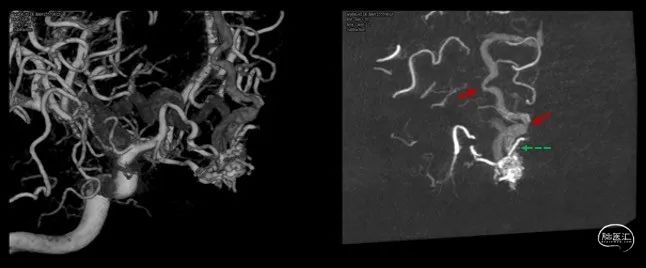

图1.当地医院CT及磁共振检查结果因故未能提供,仅提供右侧颈内动脉造影。正侧位造影显示前颅底硬脑膜动静脉瘘,右侧眼动脉参与供血,经额叶皮层静脉及额底静脉分别向矢状窦及直窦引流,引流静脉迂曲扩张。

根据病史及入院辅助检查,诊断前颅底硬脑膜动静脉瘘明确。入院后完善脑血管造影检查(图2),便于进一步分析血管构筑,制定手术策略。

详细分析患者瘘口的血管构筑学(图3),术者认为经静脉途径的优势在于:相对于动脉途径,微导管经静脉途径能够确切地到达瘘口。且该患者的引流虽经皮层及额底内侧静脉分别向矢状窦及直窦引流,但两支引流静脉均起源于一短段的引流静脉。虽然皮层引流静脉有两处走行纤细,但根据术者既往的经验,微导管通过此处并不十分困难。术中同时穿刺右侧股动脉及股静脉,将造影导管超选至右侧颈总动脉,用于实时造影、三维血管构筑分析及路图指导。同时,将Neuronmax长鞘引导至右侧横窦,6F银蛇中间导管引导至上矢状窦中份。在路图指导下,Echelon-10导管经由矢状窦-右侧额叶皮层静脉途径成功超选至右侧额底引流静脉开口,在此处放置弹簧圈,用于防止Onyx逃逸,导致静脉窦栓塞或肺栓塞,随后在静脉端使用逆向高压锅技术,注入Onyx胶,完全栓塞瘘口(图4、5)。